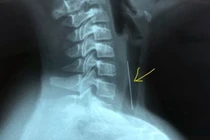

Người bệnh bị bướu cổ hơn 30 năm với kích thước khối u tuyến giáp lớn, chèn ép, đẩy khí quản cổ sang một bên gây khó thở đã được các bác sỹ Bệnh viện Nhân dân Gia Định phẫu thuật thành công.

Bị u tuyến giáp lành tính to không mổ, đến khi nuốt vướng mới đến lại bệnh viện thì u vỡ, chèn ép khí quản, thần kinh thanh quản và thực quản gây nguy hiểm tới tính mạng.

Các bác sĩ Bệnh viện TWQĐ 108 vừa phẫu thuật thành công khối u tuyến giáp khổng lồ với kích thước thùy phải 10x6cm, kích thước thùy trái 12x7cm, phát triển cả lên phía trên và đẩy xuống nền cổ, gây đè hẹp khí quản.